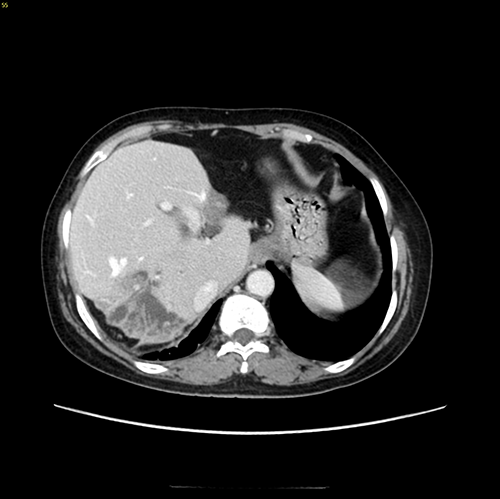

右肝后叶、左肝外侧叶胆管结石并肝萎缩、中肝肥大---右肝后叶、左肝外侧叶切除、胆囊切除